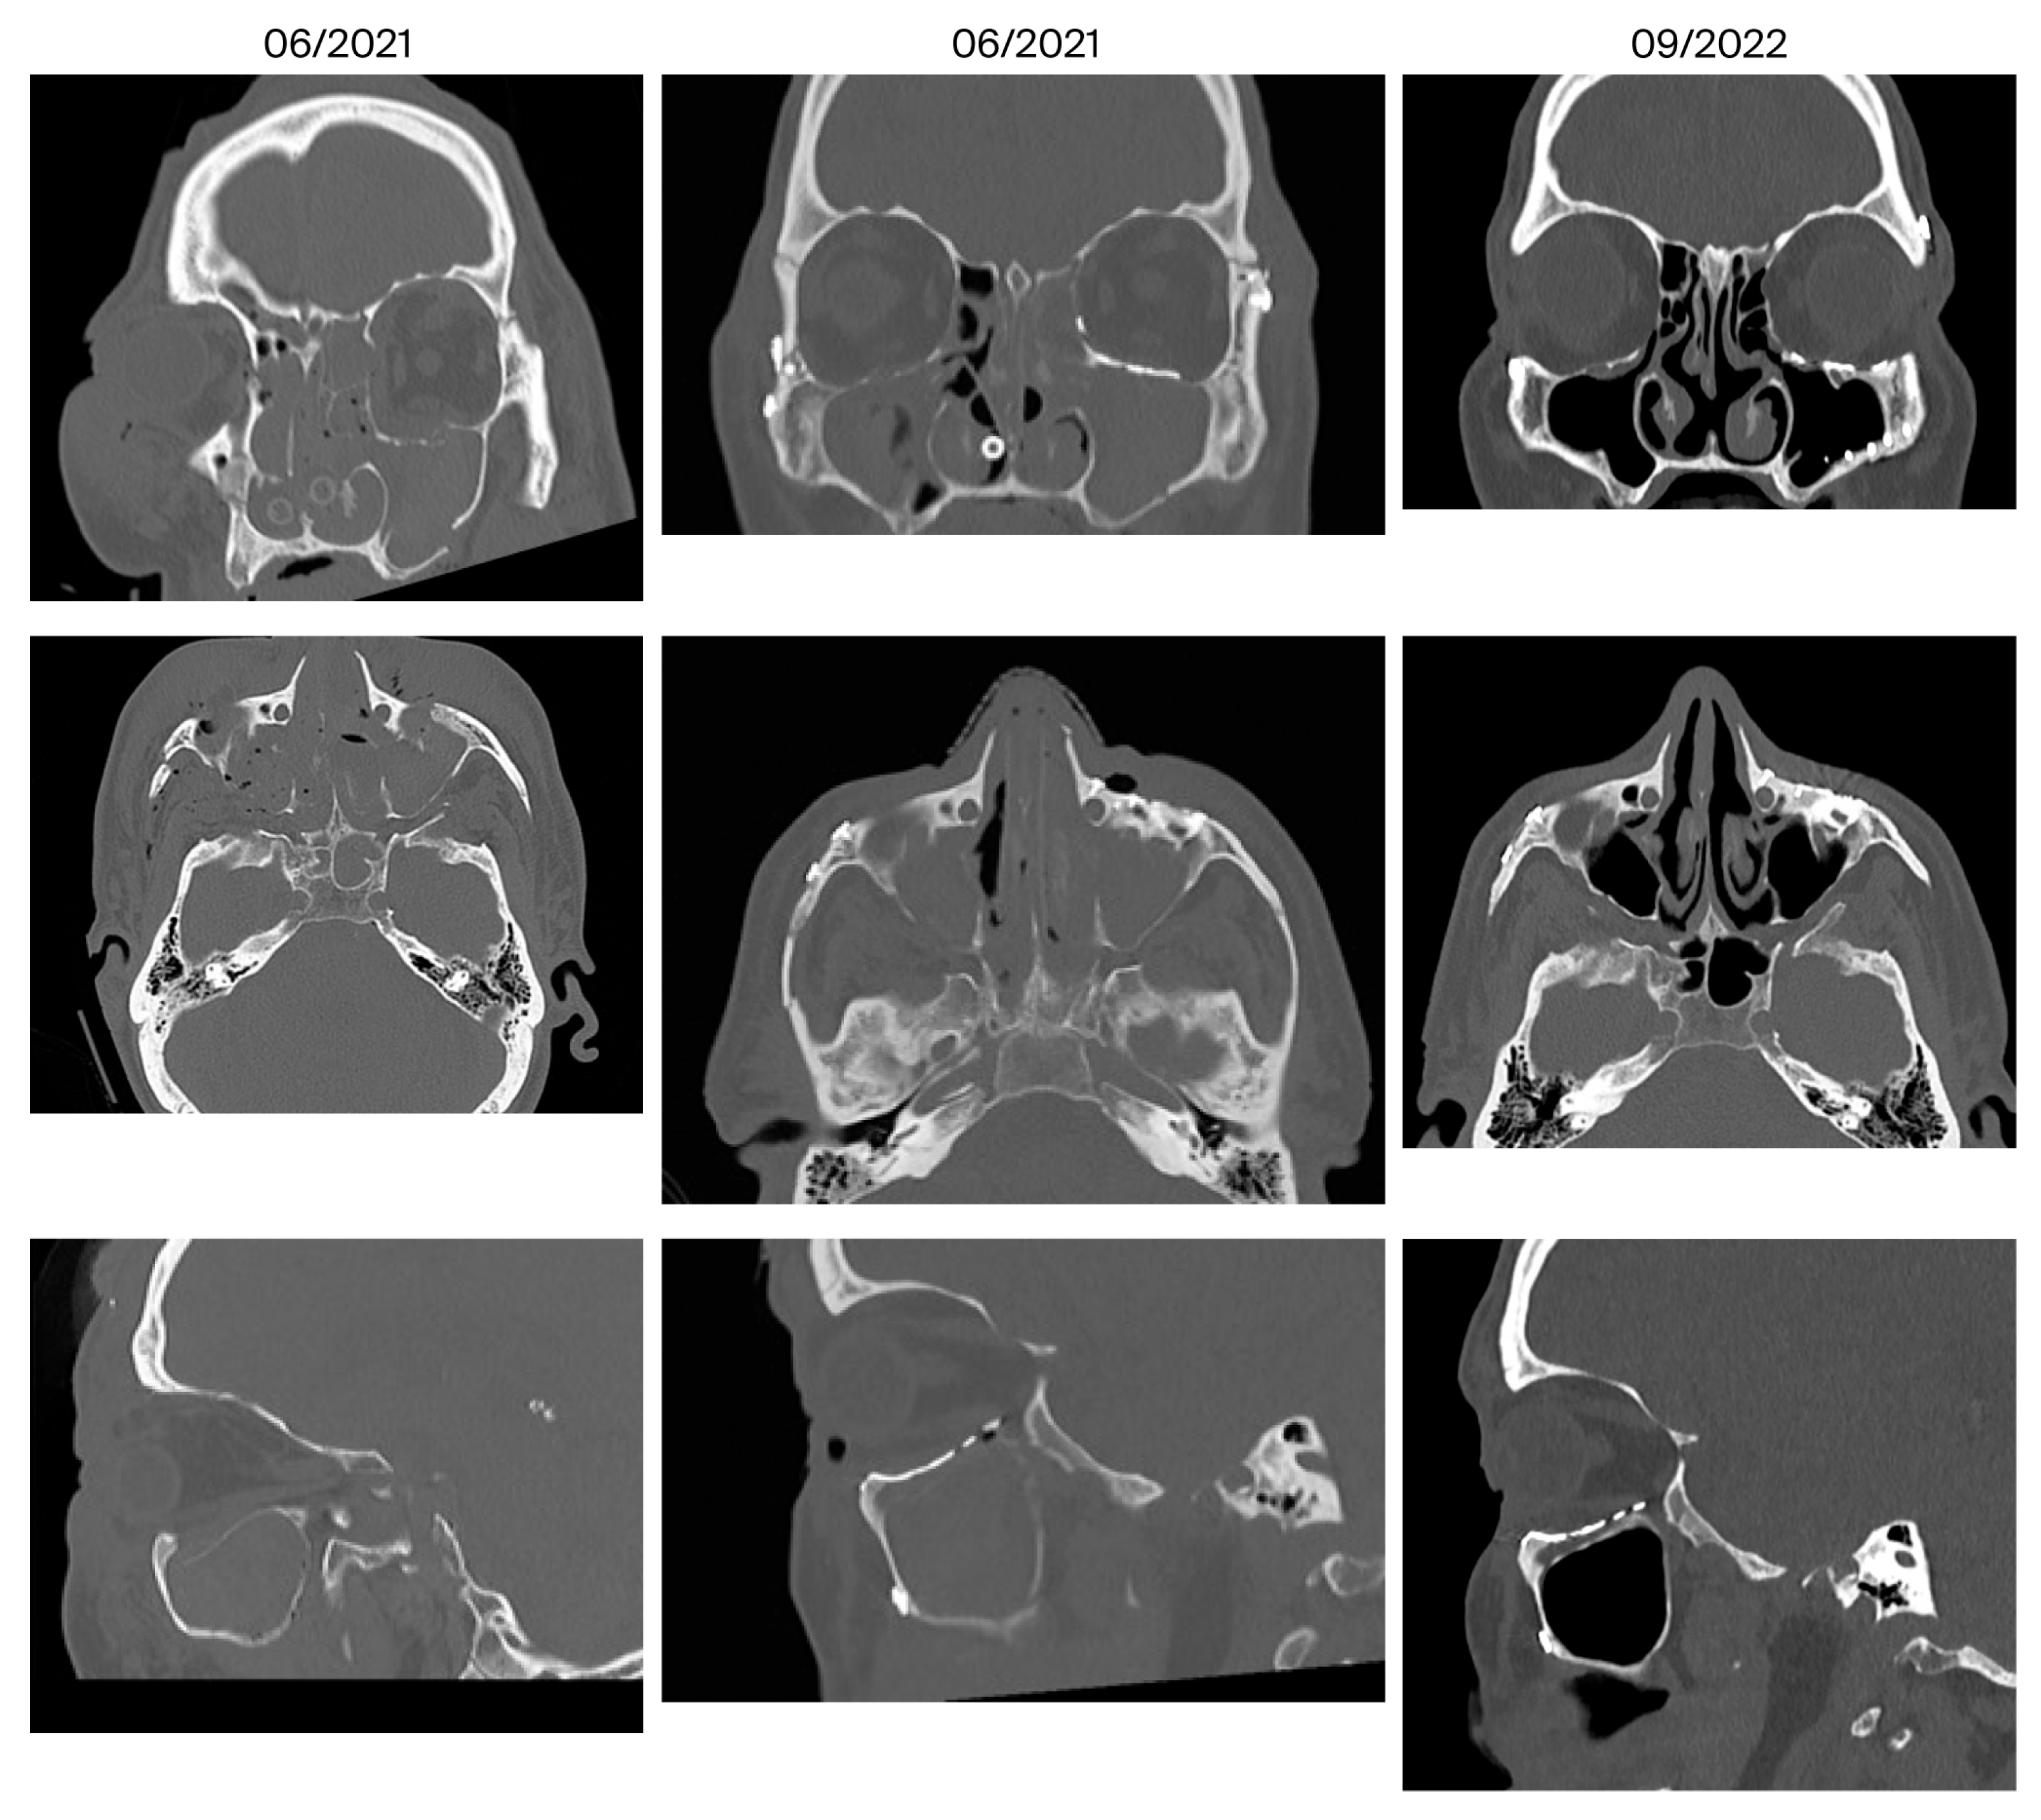

| 14 | July 2021 September 2022 (14 months) | Infraorbital hypoesthesia | No | 5/4 | No | Covered with mucosa | Minor |